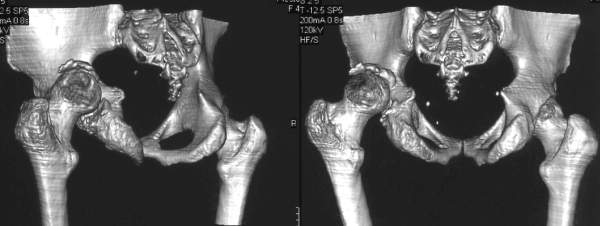

важаемые коллеги,пациент 23 лет (вес 75 кг), обратился к нам по поводу боли в тазобедренном суставе при ходьбе, нестабильность в нем при нагрузке. Ходит с тростью. 8 мес. назад попал в ДТП (никаких медицинских документов у него нет). Стоит ли открываться и вправлять вывих или сразу делать бесцементное тотальное эндопротезирование? С уважением, А. В. Вакуленко Клиника эндопротезирования суставов, г. ДонецкDear All, male patient 23 y.o., body weight 75 kg. Had RTA 8 months ago (medical records unavailable). Now has pain on motion in his left hip. On weight-bearing hip is unstable (patient use cane while walking). Keeping in mind his age, is it worth to perform open reduction? Or just do uncemented THR? Any comments are very welcome.

After 8 months, the hip will not easily come down into the acetabulum. It also appears to me that there is an impression fracture of the head of femur.

Здравствуйте. Позвольте поучаствовать в обсуждении. Поскольку пациент в течение 8 месяцев не получил адекватного лечения (видимо и по своей вине тоже), а также учитывая удовлетворительное состояние головки бедра(по данным КТ), есть смысл выполнить открытое вправление головки бедра с возможной фиксацией фрагмента заднего края пластиной. Далее начать восстановление функции сустава, дозированную нагрузку. Возможно молодой возраст пациента поможет ему отдалить время эндопротезирования. Желаю успехов.